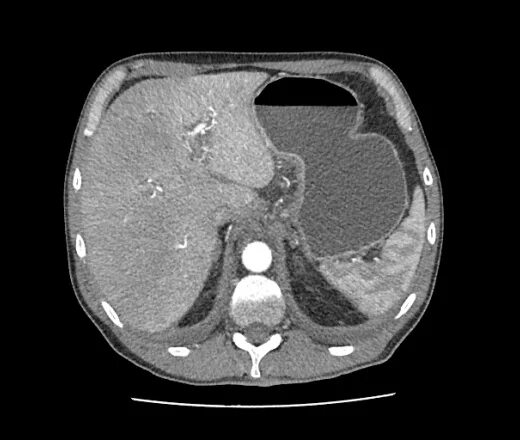

Язва желудка кт